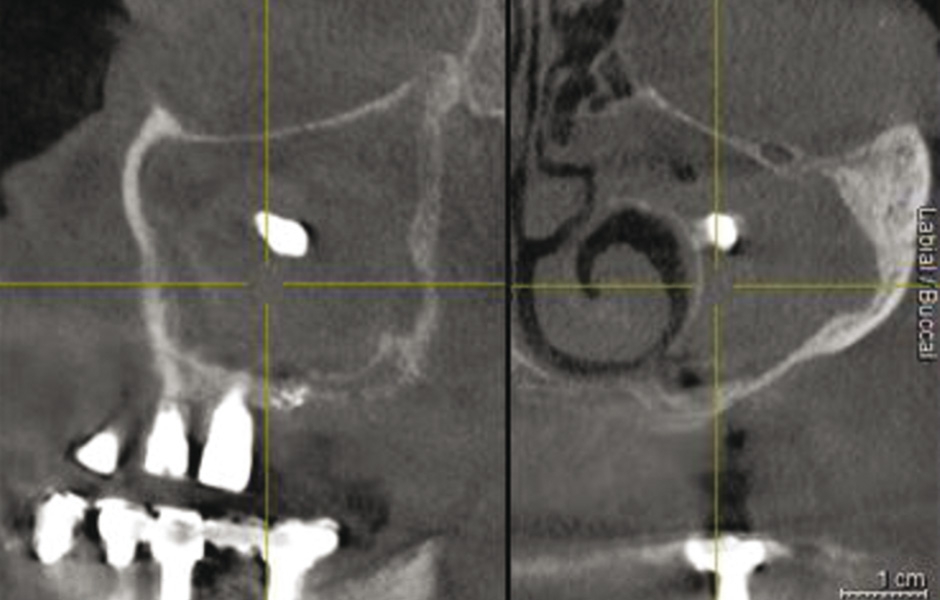

Do studie bylo zařazeno 10 pacientů s aspergilózou maxilárního sinu. U všech pacientů byl na panoramatických snímcích i na CBCT patrný radiopakní stín. CBCT navíc ukázalo, že čelistní dutina byla kompletně vyplněna homogenní patologickou masou. Chirurgická léčba sinu byla provedena za antibiotické profylaxe (Amoxicillin 2 g/den po dobu 7 dní) a intravenózní sedace (Midazolam). Kostní okénko bylo vytvořeno mikropilkou (DENTSPLY Implants), umožnilo bezpečný přístup do sinu. Po odklopení separovaného kostního fragmentu byla aspergilóza spolu s cizorodým materiálem kompletně odstraněna a dutina vypláchnuta peroxidem vodíku (H₂O₂ 3 %). Pro dodatečnou dezinfekci byla použita fotodynamická dekontaminace laserem HELBO (HELBO, Bredent Medical GmbH). Na závěr zákroku byla kostěná lamela vrácena zpět jako biologický uzávěr sinu a fixována resorbovatelnými stehy. Histopatologické vyšetření ve všech případech potvrdilo infekci aspergilózou. Po třech měsících, kdy CBCT potvrdilo nepřítomnost sinusové patologie a průchodné ostium, byla provedena augmentace kosti. Kostní bloky byly odebrány z retromolárové oblasti mandibuly a přeneseny ve 3D konfiguraci podle split-bone block techniky v kombinaci se sinus liftem. Sinus byl augmentován autologní kostí a biomateriálem (FRIOS Algipore®, DENTSPLY Implants) vrstvenou technikou. Po dalších třech měsících byly do augmentované oblasti zavedeny implantáty. O další tři měsíce později byly implantáty odhaleny a následně byla zhotovena definitivní protetická náhrada.“

Obr. 1: CBCT: radiopakní stín v levém maxilárním sinu.